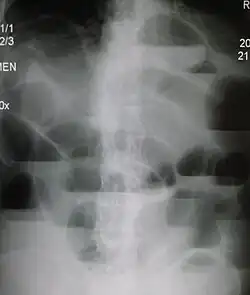

Die körperliche Untersuchung einschließlich rektaler Untersuchung ergibt mit lokalen Schmerzen, Abwehrspannung, Hernien (Eingeweidebrüche) und Überblähung wichtige Hinweise. Zusätzlich erfolgen Blutentnahme zur Bestimmung von Laborwerten sowie Bildgebung mit Sonographie und eventuell Röntgen des Abdomens.

Die Röntgenleeraufnahme des Bauchs im Stehen oder in Linksseitenlage zeigt beim typischen Ileus überblähte Darmschlingen mit Flüssigkeitsspiegeln als Hinweis auf den Ort eines Verschlusses. Je nach Befinden können durch einen Einlauf und/oder eine Passage mit Kontrastmittel Ort und Ursache eingegrenzt werden.

Zusätzlich kann eine CT des Bauchs durchgeführt werden. Damit kann häufig die Ursache des Darmverschlusses gefunden werden.